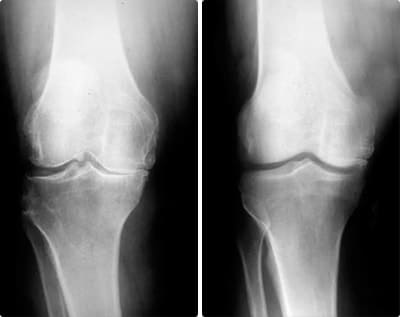

Las lesiones pueden variar en complejidad, pero se pueden agrupar en dos tipos: musculares y articulares. Esguinces, desgarros, osteoartritis crónica. Los riesgos son inevitables si no te proteges a tiempo.

El fútbol es un deporte extremadamente traumático. Las rodillas, las pantorrillas y el pie están constantemente en riesgo. Lo pasé por todo durante mi carrera: desde la distensión de los músculos de la pierna hasta el daño del menisco. Es imposible defenderse de todo, siempre tengo Сortitron a mano durante el período de rehabilitación.